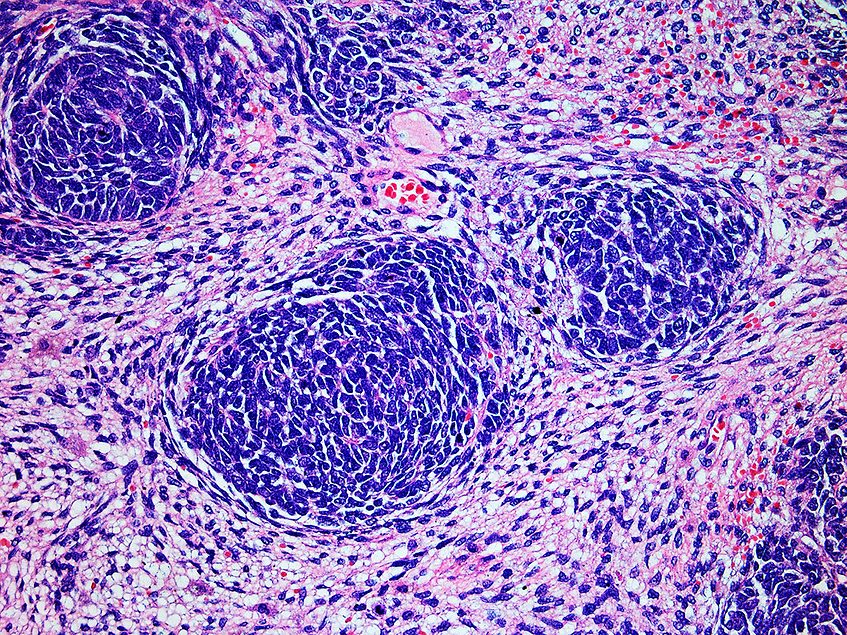

AbbVie’s ADC win shows how pharma can break through in solid tumors

Antibody-drug conjugates have become a “choose your own adventure” tool in pharma R&D. Due to their versatility, the therapies have proved themselves as a potent weapon against many oncology indications, AstraZeneca’s vice president and head of …